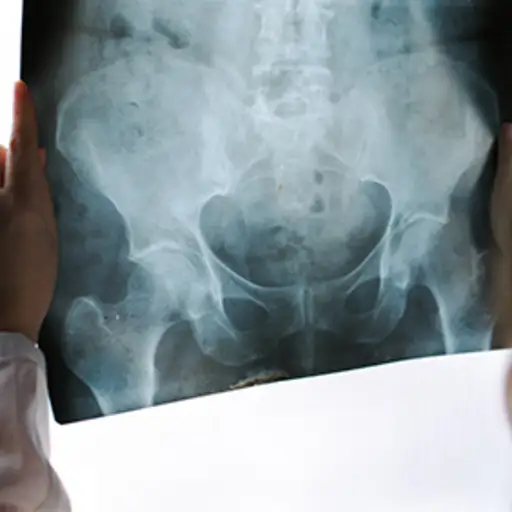

强直性脊柱炎博士,病房博士说,慢性炎症性关节炎的一种形式,百分之一(0.5%)。“这种疾病的发病率没有重大变化,因为它主要由遗传学决定。许多患有迹象和症状的人,尽管多年来一致,但尚未显示确认作为诊断所必需的骨骼变化。”通常通过分析X射线上的脊柱和骨盆的变化来诊断该病症。

大多数AS患者有终生的症状和一定程度的脊柱融合。沃德医生说:“很小一部分人可能会患上AS,然后就停止了。”其他人有症状,但x光片上没有进展。“我们不能完全理解,因为他们有症状,但这就是我们看到的——这是同一种疾病或一种类似于。最新的基因研究表明,AS存在一种“基因特征”,但我们越深入研究,就越觉得不清楚。还有更多的工作要做。”